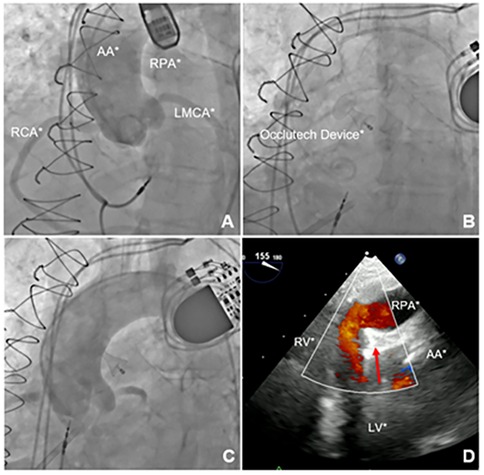

The procedure was performed through a right common femoral artery puncture. The arterial approach was preferred because accessing the fistula from the higher-pressure aortic side toward the lower-pressure pulmonary artery was technically more feasible. A 6-Fr pigtail catheter was used for aortography to identify the fistula and determine its location, although its exact location could not be precisely identified (Figure 2A and Supplementary Video S4).

Figure 2

Imaging of the aortopulmonary fistula correction procedure. (A) Aortography demonstrating contrast flow to the right pulmonary artery. (B) PDA occluder deployed. (C) Control aortography demonstrating absence of flow to the right pulmonary artery. (D) TEE confirming absence of flow between the aorta and right pulmonary artery with the device successfully deployed (red arrow). AA, ascending aorta; MPA, main pulmonary artery; LPA, left pulmonary artery; RPA, right pulmonary artery; LMCA, left main coronary artery; RCA, right coronary artery; RV, right ventricle; LV, left ventricle.

Attempts at selective catheterization under TEE guidance were made using 6-Fr Judkins Right (JR) 4.0, 6-Fr Multipurpose 2.0, and 6-Fr Amplatz Left 1.0 catheters. However, these attempts were unsuccessful, likely due to the high and anterior position of the fistula, which made it difficult to align the catheters with the fistulous orifice. Thus, puncture of the right radial artery provided a more favorable catheter angle within the ascending aorta, allowing the fistula to be successfully crossed using a 6-Fr JR 4.0 catheter and a 0.014-inch guidewire. Nevertheless, selective catheterization remained challenging due to the difficulty in precisely identifying the fistulous opening.

After crossing the fistula with the JR catheter, a long 0.035-inch hydrophilic guidewire was advanced into the right pulmonary artery and further into the inferior vena cava, where it was snared using an endovascular Snare system through the right femoral venous access. This approach enabled the introduction of a 7-Fr delivery system via the venous access, through which the Occlutech PDA Occluder 8/10 was successfully deployed from the pulmonary artery toward the aorta. This strategy allowed for optimal sealing of the aortic–pulmonary communication while maintaining delivery through the venous access.

The device was successfully deployed in an optimal position, achieving complete closure of the fistula (Figures 2B,C and Supplementary Video S5). Postprocedural TEE confirmed the absence of peridevice leaks (Figure 2D and Supplementary Video S6). The patient was discharged with significant improvement in symptoms, no longer requiring diuretic therapy, and was transitioned to a direct oral anticoagulant due to poor adhesion to coumarin.